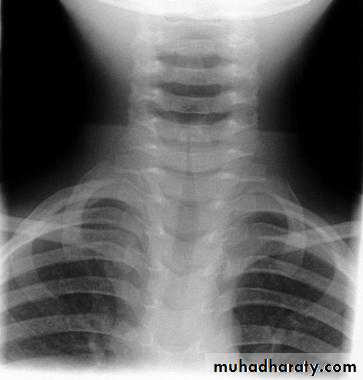

• The onset is usually preceded by a simple sore throat, with slight fever and irritating cough ' 1. Cough. A laryngeal spasm (‘false croup’) develops suddenly.• 2. Dyspnoea, cyanosis and stridor. From laryngeal spasm and mucosal oedema, the latter sometimes extending to the subglottic space. ‘Laryngitis stridulosa ’ is the name given to the condition when stridor is present. It is inspiratory and indrawing of the supra- and infra-clavicular fossae may be present during the paroxysms of stridor.

• Acute laryngbtracheobronchitis

• Are those of an acute simple laryngitis as it occurs in children, but are much more severe.• 1. Hard, dry, croupy cough and hoarseness. Occur after a cold or influenza.

• Acute epiglottis

• Definition• Special form of acute laryngitis, in- which the inflammatory changes affect mainly the loosely attached mucosa of the epiglottis.